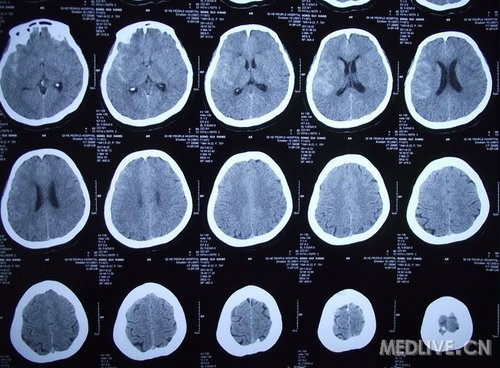

脑出血图片

形形色色脑出血

脑出血